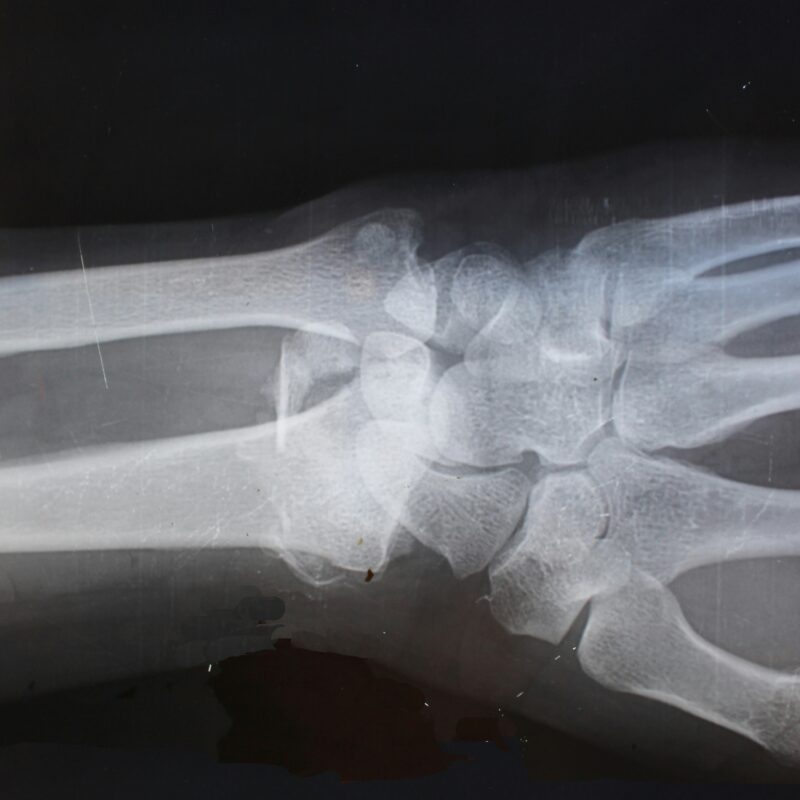

- Common Orthopedic Injuries Treated at a Local Urgent Care